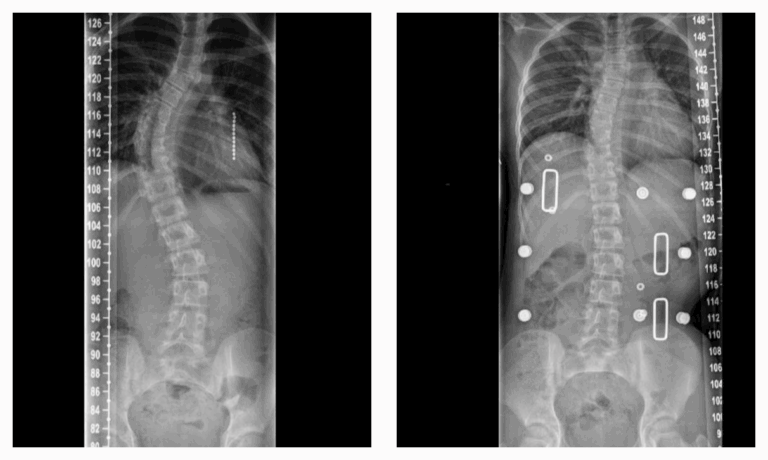

Een röntgenfoto geeft jouw behandelend orthopedisch chirurg exacte informatie over de ernst van de kromming. Op basis daarvan wordt samen met je ouders en jou besloten welke behandeling het meest geschikt is.